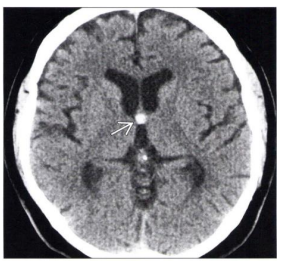

Tomografia do crânio sem

contraste em corte axial ao nível do

forame de Monro demonstra a

imagem apontada pela seta na figura

abaixo. O diagnóstico CORRETO é: